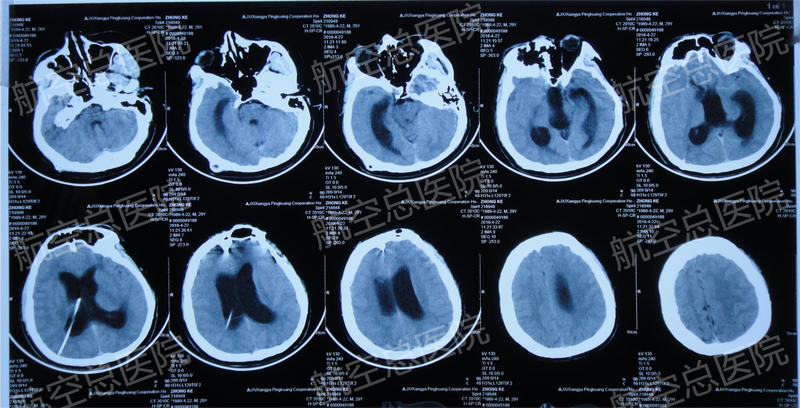

小宇(化名)今年28歲,來自江西的一個帥小伙,在北京一家公司上班。青春正盛的小宇在北京努力打拼,憧憬著未來的美好生活??墒敲倦y測,誰都不知道意外哪一天會降臨!?28歲小伙突發(fā)腦出血、腦疝,命懸一線、生死難料小宇是公司的業(yè)務(wù)骨干,有時加班到很晚,作息很不規(guī)律,工作壓力比較大。好在他有打籃球的愛好,偶爾運動一下,可以釋放一下壓力,舒緩一下心情。那天下午,他去打了場籃球,痛快淋漓。第二天上班后,他卻突然感覺到有些頭痛頭暈,便跟領(lǐng)導(dǎo)請了假回家休息,還買了些感冒藥吃了??墒且惶觳灰姾?,兩天不見好,他還是不斷地頭痛頭暈,昏昏沉沉,甚至有些意識模糊。公司同事見他兩天沒來,擔(dān)心他出事,便通過公安局查到他的住址。同事找到小宇住處時,他意識狀態(tài)已經(jīng)非常不好,同事趕緊送他到附近的航空總醫(yī)院就診,并聯(lián)系了小宇遠(yuǎn)在江西的家人。到醫(yī)院做檢查的過程中,小宇已經(jīng)基本沒有意識,什么都不記得了。經(jīng)頭顱CT檢查診斷為顳頂葉腦出血,可疑靜脈竇血栓?進(jìn)一步排查腦血管,發(fā)現(xiàn)顱內(nèi)靜脈竇血栓,而腦葉出血正是由靜脈竇血栓繼發(fā)。小宇收入航空總醫(yī)院神經(jīng)內(nèi)科,給予藥物保守治療,但兩天后患者癥狀加重,已經(jīng)完全昏迷,右側(cè)瞳孔散大,再次行CT檢查提示腦水腫加重、腦疝形成。情況已經(jīng)十分危急,需要轉(zhuǎn)神經(jīng)外科進(jìn)行手術(shù)治療。醫(yī)生向家屬交代病情:目前患者病情危重,如果不及時進(jìn)行開顱手術(shù)治療,患者隨時會有生命危險,家屬同意手術(shù),手術(shù)談話和簽字是由小宇的妹妹和妹夫完成。隨后,航空總醫(yī)院創(chuàng)傷腦血管病神經(jīng)外科楊凱副主任醫(yī)師和申俊峰主治醫(yī)師為小宇實施右側(cè)額顳頂血腫清除術(shù)+去骨瓣減壓術(shù),成功挽救了小宇的生命。而手術(shù)室外,小宇的家人一直在焦急地等待。他母親在門口一直以淚洗面,而父親在一旁也手腳發(fā)抖,頭腦發(fā)懵。他母親事后哭訴著回憶,“從病房送手術(shù)室的路上,我一直叫我兒子,他一點反應(yīng)都沒有,我就特別害怕,特別擔(dān)心。手術(shù)過程中,我們在門外也是特別著急,心都是一直懸著的,我們也不知道他能不能下手術(shù)臺?!?病情罕見危重,航空總醫(yī)院神經(jīng)外科綜合系統(tǒng)診療成功挽救生命當(dāng)手術(shù)結(jié)束,楊凱醫(yī)生走出手術(shù)室,告訴她們手術(shù)成功,她們這才稍稍放松一點。手術(shù)效果很好,術(shù)后當(dāng)晚小宇意識恢復(fù)清醒,呼吸機(jī)脫機(jī),氣管插管拔除,患者神清語利。之后的幾天狀態(tài)也都不錯,還可以進(jìn)食一些水果,家屬也很高興。然而小宇還并沒有完全脫離危險。開顱手術(shù)為小宇清除了腦血腫,降低了顱內(nèi)壓,緩解了腦疝,但是小宇的原發(fā)病顱內(nèi)靜脈竇血栓還需要進(jìn)一步治療。開顱術(shù)后第四天,航空總醫(yī)院創(chuàng)傷腦血管病神經(jīng)外科金永健主任、穆蒼山副主任召集科室腦血管病組、神經(jīng)重癥組、神經(jīng)介入組、顱腦創(chuàng)傷組、整形修復(fù)組等相關(guān)專家會診討論,制定了周密的后續(xù)治療方案。科室唐璽和博士和張波副主任醫(yī)師為小宇實施神經(jīng)介入靜脈取栓術(shù),通過神經(jīng)微導(dǎo)管從乙狀竇經(jīng)橫竇取出約21cm大小血栓,然后用球囊擴(kuò)張疏通血管和腔竇,術(shù)后保留鞘管持續(xù)尿激酶接觸性溶栓7天。唐璽和博士介紹,這是目前國內(nèi)十分先進(jìn)的神經(jīng)介入治療技術(shù),在北京也僅有幾家醫(yī)院可以開展。在溶栓治療的同時,楊凱副主任醫(yī)師指導(dǎo)為小宇進(jìn)行亞低溫腦保護(hù)治療,使用一定的技術(shù)手段將患者腦部溫度降至34℃左右,以降低機(jī)體的代謝,減輕機(jī)體的過度應(yīng)激反應(yīng),減低細(xì)胞的耗氧量,改善微循環(huán),避免細(xì)胞遭受嚴(yán)重的損害,使機(jī)體避開危險渡過難關(guān),為小宇靜脈竇血栓和腦損傷的治療爭取時間。經(jīng)過科室整個團(tuán)隊十余天的綜合系統(tǒng)治療,小宇情況逐漸穩(wěn)定,意識狀態(tài)恢復(fù)良好,四肢無活動障礙,順利出院,到康復(fù)醫(yī)院進(jìn)行后續(xù)的康復(fù)治療。這個病例的成功救治,是航空總醫(yī)院創(chuàng)傷腦血管病神經(jīng)外科日常工作的常態(tài),創(chuàng)傷、介入和神經(jīng)重癥等各個神經(jīng)外科亞專業(yè)有機(jī)結(jié)合的結(jié)果。?PEEK顱骨修復(fù)整形,恢復(fù)完美外觀,重塑人生自信一個28歲的小伙子,突然遭遇這樣的重病,這對于小宇來說,是非常不幸甚至是殘酷的;但是,在那樣危重的情況下,小宇遇到專業(yè)的醫(yī)療團(tuán)隊,成功挽救了他的生命,無疑又是幸運的。前期的治療是非常成功,經(jīng)過康復(fù)治療,小宇已經(jīng)可以恢復(fù)正常的生活和工作了。但是,當(dāng)時急診手術(shù)為了緩解顱內(nèi)壓力而不得不進(jìn)行的去骨瓣手術(shù),術(shù)后遺留下了顱骨缺損的問題。這對小宇的生活多少產(chǎn)生一定的困擾和影響,每每照鏡子看到自己的頭顱,他感覺好像頭缺了一塊,對形象影響很大,內(nèi)心不由得有些沮喪;同時他日?;顒右惨中⌒闹?jǐn)慎,避免磕碰,避免銳物撞擊;他彎腰的時候還會有頭痛、頭暈的癥狀,他能明顯感覺到頭皮是塌下去的,覺得很不自然。而小宇的母親看著兒子缺損的頭顱,看到他頭上的凹坑,內(nèi)心一直都是揪著的,一直都很害怕,每每傷心落淚。不過對于這些,小宇倒也沒有過多的擔(dān)心,因為當(dāng)時出院前,醫(yī)生就告訴他后期還可以做顱骨修復(fù)。出院后大約三個月,小宇再次來到航空總醫(yī)院創(chuàng)傷腦血管病神經(jīng)外科,準(zhǔn)備接受顱骨修復(fù)整形手術(shù)。科室穆蒼山主任醫(yī)師帶領(lǐng)團(tuán)隊科學(xué)評估,為其定制了個性化三維塑形、3D打印制作的PEEK(聚醚醚酮)修補材料,并制定周密的手術(shù)計劃。隨后穆蒼山主任醫(yī)師主刀、楊凱副主任醫(yī)師協(xié)助順利為他施行PEEK顱骨修復(fù)整形手術(shù)。術(shù)中,PEEK精準(zhǔn)嵌合于骨窗,嚴(yán)絲合縫,復(fù)位良好。經(jīng)過約3個小時,手術(shù)順利完成。顱骨修復(fù)手術(shù)非常成功,術(shù)后復(fù)查CT顯示顱骨復(fù)位滿意,PEEK與骨窗對位對線良好,各層組織解剖層次清晰。小宇原先塌陷的頭皮重新膨隆飽滿起來,外觀恢復(fù)如初。小宇高興地說:“等頭發(fā)長起來,就和以前一樣了,我還是比較有信心的?!?臨出院,患者及家屬感謝醫(yī)療團(tuán)隊給他第二次生命小宇的母親說:“整個治療真的是很成功,航空總醫(yī)院創(chuàng)傷腦血管病神經(jīng)外科整個團(tuán)隊都付出了巨大的努力,所有的人都在參與,用他們專業(yè)的、精湛的技術(shù)保住了我兒子的命,真的謝謝他們,感謝所有的醫(yī)生護(hù)士們,還有關(guān)心我們的醫(yī)院領(lǐng)導(dǎo)?!彼f,這里的大夫不僅是醫(yī)好了小宇,同時也醫(yī)好了半個她,如果兒子有事,她可能一輩子都過不安心,會失去半條命,所以這等于是挽救了他們整個家庭,說著她再度落淚。小宇說:“現(xiàn)在要出院了,感謝金主任、穆主任、楊醫(yī)生、申大夫、唐博士、張大夫等所有的醫(yī)護(hù)人員,感謝你們,你們的醫(yī)品、醫(yī)德都非常值得大家尊敬,你們的醫(yī)術(shù)非常精湛,再次說一聲感謝,感謝你們給我第二次生命?!?